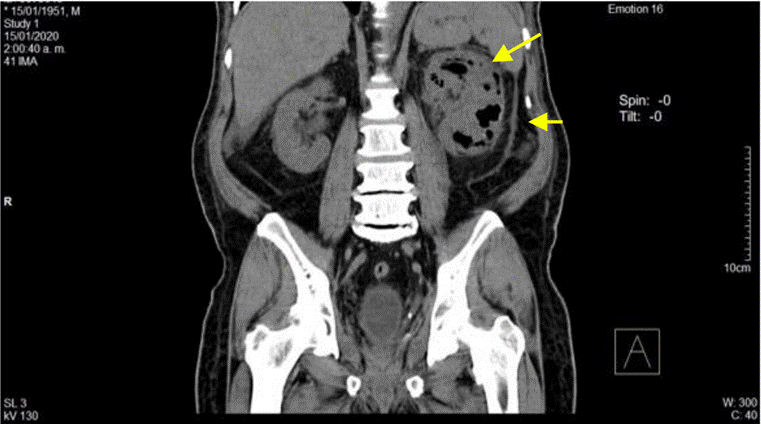

La ecografía abdominal total mostró hallazgos sugestivos de PNE izquierda (Figura 1), por lo que se solicitó valoración por urología; este servicio indicó continuar con la misma terapia antibiótica y realizar UROTAC que mostró microlitiasis renal bilateral, litiasis ureteral izquierda y proceso infeccioso inflamatorio con presencia de gas en el riñón izquierdo, lo que indicó diagnóstico de PNE izquierda tipo 2 (Figuras 2 y 3). Ante los hallazgos radiológicos y el reporte de urocultivo positivo para Escherichia coli multisensible, se decidió hacer rotación de cubrimiento antibiótico a carbapenémicos debido al alto riesgo de mortalidad.

Fuente: documento obtenido durante la realización del estudio.

Figura 3 UROTAC en el que se evidencia riñón izquierdo de mayor tamaño con destrucción del parénquima y sustitución por material gaseoso.